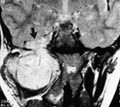

MR-urografi har potensial til å kunne erstatte tradisjonelle røntgenologiske metoder som urografi, CT-urografi og kanskje også scintigrafi hos barn. Strålehygienisk sett er dette viktig (11). Anomalier som agenesi, hypoplasi og dysplasi, dobbeltanlegg, ektopi og hesteskonyre lar seg enkelt fremstille. Solitære og multilokulære cyster, eventuelt komplisert med blødning, multicystisk nyre, infarkt, infeksjon eller abscess, arrforandringer og tumor diagnostiseres med stor sikkerhet. Ved å gjøre dynamisk kontrastundersøkelse med bilder hvert 2. – 3. sekund i tillegg til den morfologiske utredningen vil man kunne få et visuelt inntrykk av nyrefunksjonen (fig 5). Oppladningsmønsteret kan visualiseres i bark og marg. Obstruksjoner i samlesystemet kan studeres ved å måle signalintensiteten over tid i nyrebekkenet etter furosemidbelastning (12). CT gir imidlertid bedre fremstilling av forkalkninger og også ofte bedre fremstilling av nyrevenen enn MR.

Overflatespoler kan være egnet for detaljdiagnostikk i perineum og det lille bekken, f.eks. ved utredninger av anorektale eller urogenitale skader og misdannelser. Anorektale anomalier inkluderer ektopisk anus og høy eller lav analatresi og -stenose. MR er først og fremst nyttig for kartlegging av atresinivå i forhold til levatormuskulaturen, og intakt sfinkterapparat kan verifiseres med MR før en eventuell gjennomtrekningsoperasjon. Det er også mulig å kontrollere at operasjonen er korrekt utført med MR, og skille ut de sjeldne tilfeller der asymmetrisk plassering av analkanalen i forhold til muskulatur eller interposisjon av fettvev er årsak til postoperativ inkontinens. En rekke arbeider har påvist nytten av MR ved kartlegging av fistler i ulike lokalisasjoner, spesielt der det er sparsomt med sekresjon (13).